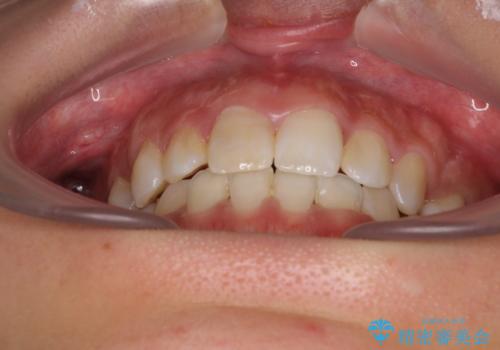

- 八重歯や前歯のデコボコを気にして来院された患者様です。

目立たない装置を希望されたので、上顎が裏側装置のハーフリンガルを選択し、上下左右の小臼歯(計4歯)を抜歯して矯正治療を行うこととしました。

裏側装置での矯正治療は、上顎前歯の正中のズレをまっすぐに改善することが難しいのですが、きれいに整えることができました。